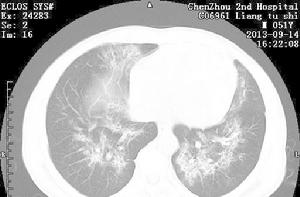

PCP型肺炎是非常重要的機會感染症,也是愛滋病最常見的併發症和愛滋病患者主要死亡原因之一,必須及時診斷、預防和治療。初期症狀以因低氧血症出現進行性呼吸障礙為特徵,特別是勞動時出現氣喘、呼吸困難、乾性咳嗽、發熱等症狀 。